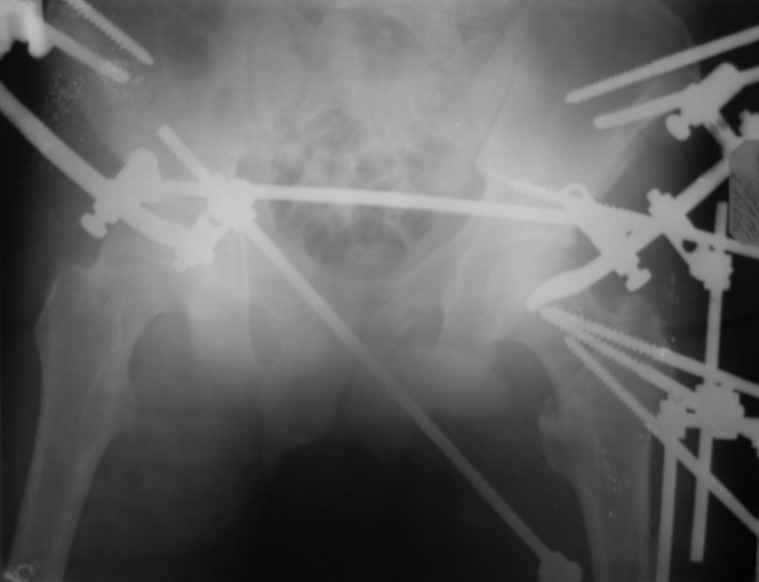

Если снимок справа по хронологии последний, то в тазобедренном сустава наступил анкилоз. Это хороший плюс костной ткани для постановки чашки эндопротеза, но отсутствие сохранения биомеханической оси бедренной кости ставит под вопрос благоприятный вариант усановки ножки эндопротеза.... Учитывая выполненную остеотомию, не считаю выполнение скелетного вытяжения лишенным смысла, для восстановления оси конечности с последующим, возможно, индивидуальным эндопротезированием.

Вот снимки по свежей ситуации, парень 19 лет, длинный оскольчатый перелом бедра от шейки до в-с/3. давно уже ходит на своих ногах.

Представленные Вами рентгенограммы действительно являются примером качественной фиксации спице-стержневым аппаратом. Они, как ни что другое, многое иллюстрируют.

Кроме того, было бы ошибкой ставить знак равенства между нашим и Вашим пациентами. Они не только не похожи, разница между ними просто огромная. Говорю это не для того, чтобы задеть Вас или обидеть. Ни в коем случае. Просто теперь я понимаю, что Ваше мнением строится на простом преломлении Ваших подходов к лечению пациентов со свежими переломами, на ситуацию, абсолютно несопоставимую, подобную нашей.

Компоновку данного аппарата, в котором дистальный отломок фиксирован лишь на дистальном уровне, а проксимальный вообще сам по себе никак, только через бывший сустав, назвать стабильной никак нельзя. Нет стабильности - нет нормального заживления, но есть осложнения, надеюсь, это-то можно экстраполировать на вашего больного?